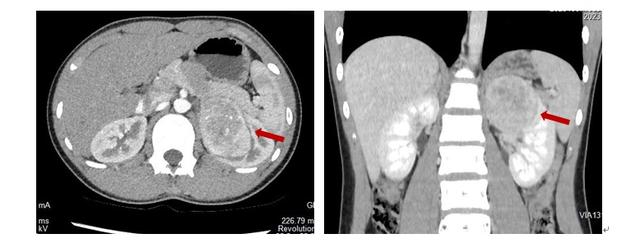

无独有偶,另一名14岁女孩若若偶然发现左肾大肿瘤,最大径约7.7cm,增强CT检查提示为肾脏恶性肿瘤。家长带着若若焦急地辗转于多家医院,均被告知需行左肾根治性切除,无法保肾。

通过医生的推荐,若若父母找到了新华医院崔心刚教授。崔教授通过充分的术前评估,制定了详细的手术方案,通过达芬奇机器人手术顺利进行了保肾手术,若若术后恢复良好。